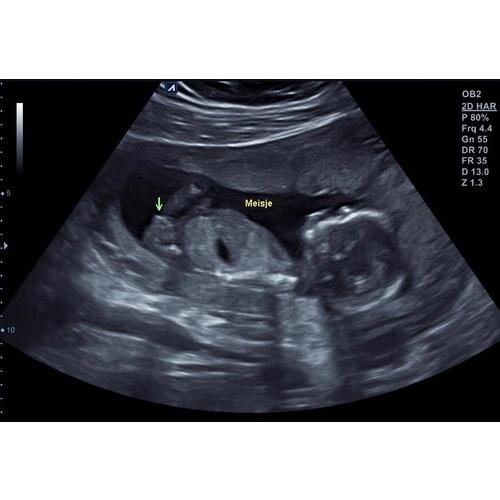

Bij 13w en 5 dagen zag je het ook vanaf zijkant en deze echo is 14w en 6 dagen

Ik was daar 14 weken en 6 dagen😊